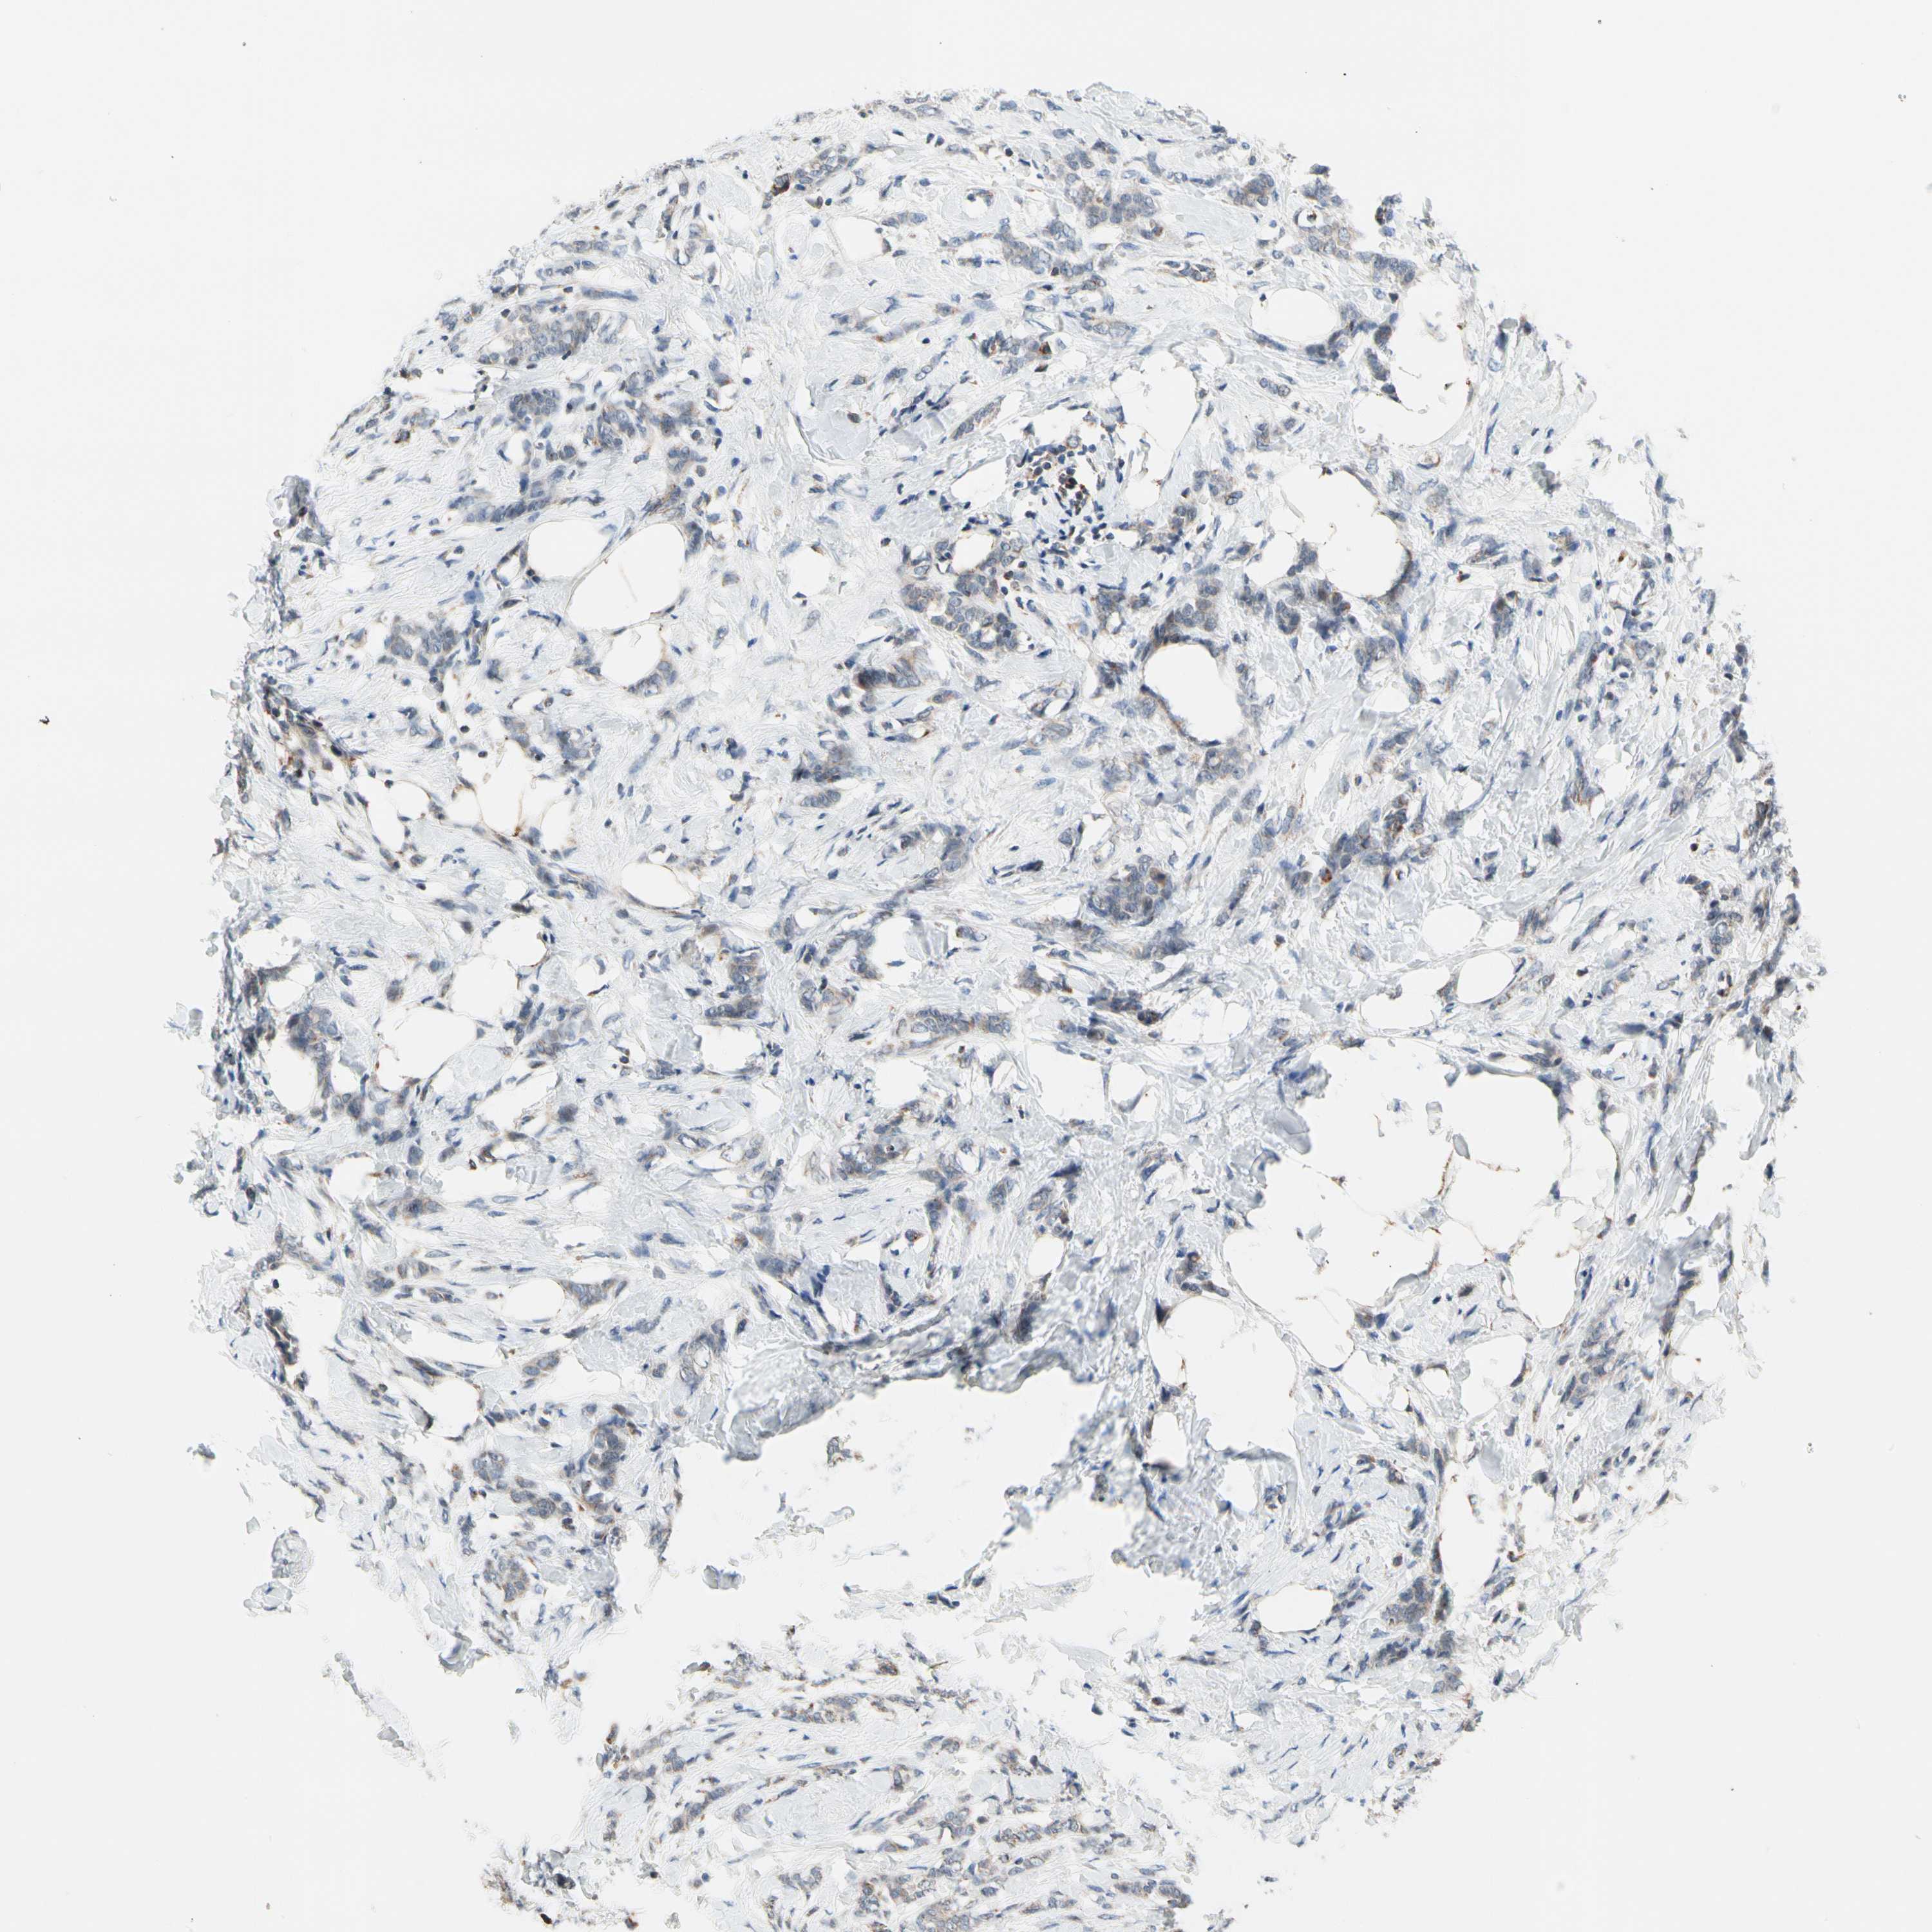

CANCER BREAST CANCER Show tissue menu

Breast cancer

Human cancer